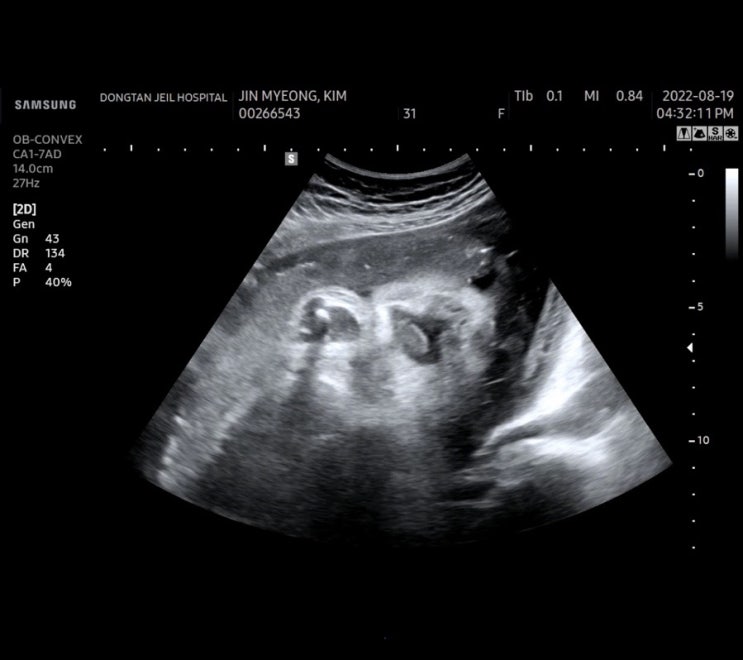

38주 6일차 호떡이 동탄제일병원에서 검진기록 (오늘도 초음파검사) #디데이 8일남았다, 오늘하루기록

38주 6일차 오늘은 병원 가는날 이제 호떡이 만나는날이 일주일 정도 남았는데 아직 소식 없는 호떡이 언제...